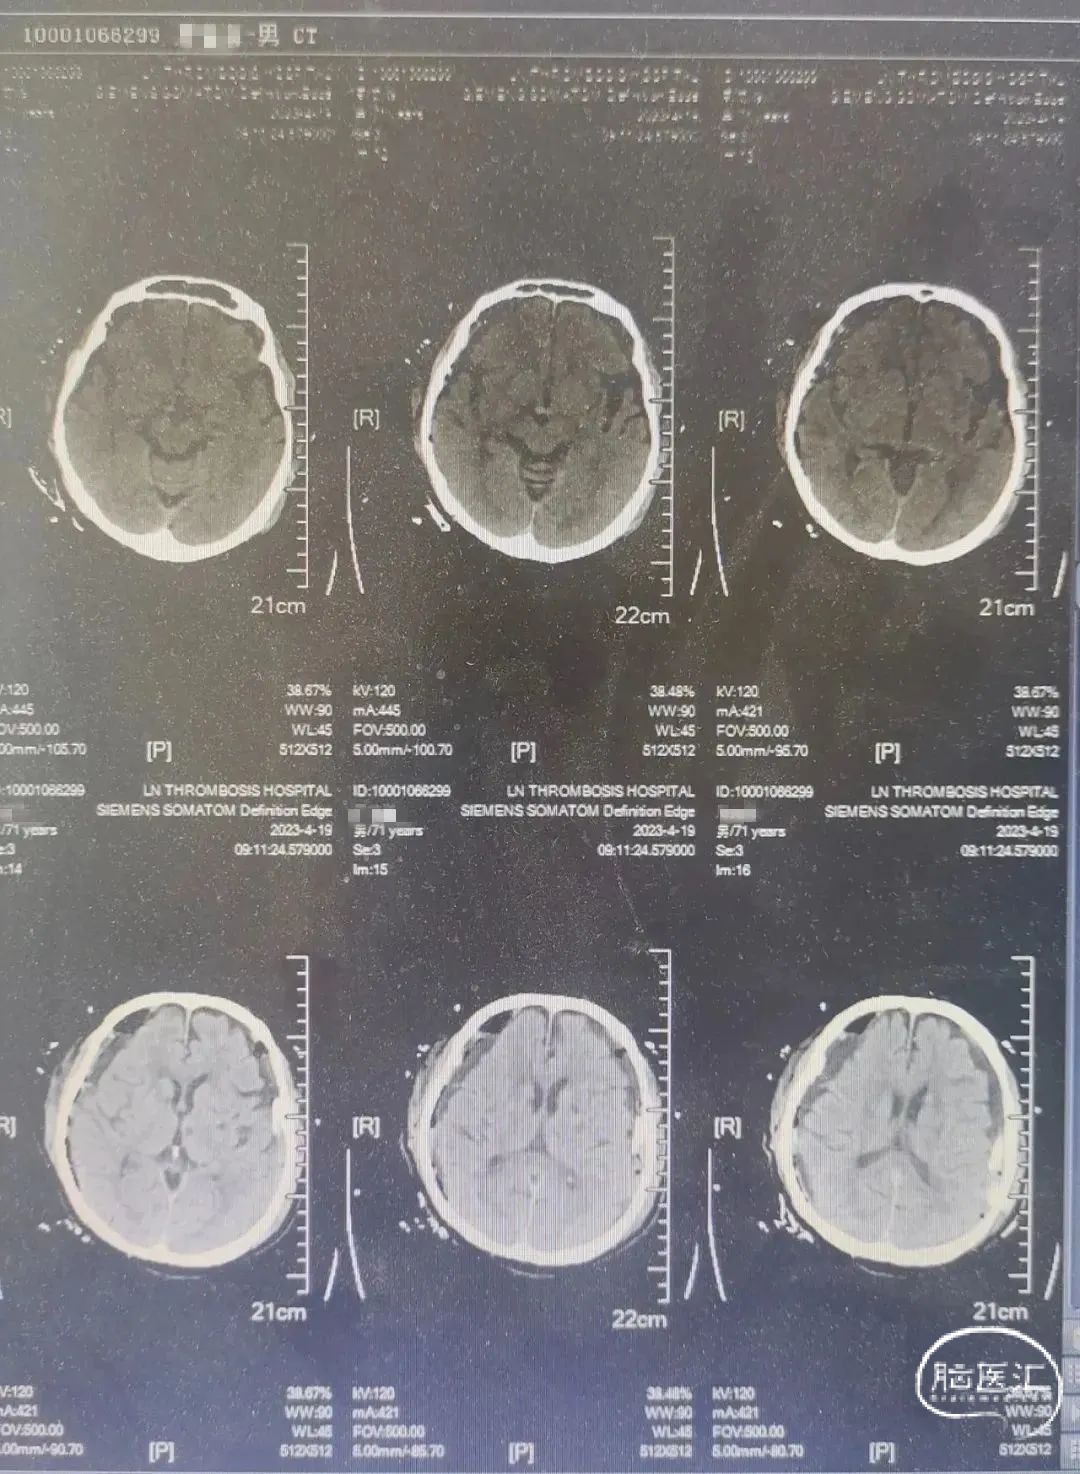

术前CT

术前CT